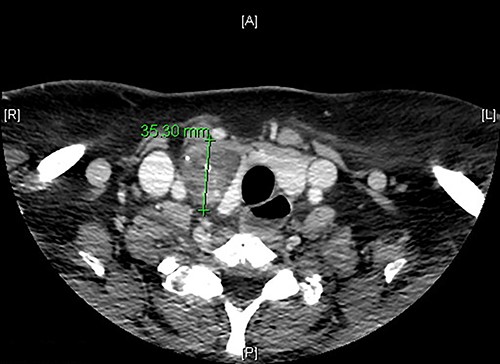

We present the case of a 51-year-old female patient who was recently diagnosed with myasthenia gravis and consults with a right thyroid nodular lesion, discovered incidentally in a CT. The initial suspicion by imaging is ectopic thymoma. It is a well-defined, hypodense nodule, 4.5 × 3.3 × 2.5 cm, associated with intralesional calcifications, which seems to compress the right thyroid lobe extrinsically (Fig. 1). However, more cranially, it seems to present a union pole with the right lobe, which could correspond to an eccentric thyroid nodule. We carried out adirected study of the neck and thyroid. The patient denied compressive symptoms, dyspnea or voice changes. On examination, the patient presented a palpable nodule in the right thyroid lobe, soft and mobile. US study shows a hypoechoic heterogeneous nodular image, 5.5 × 3.1 cm in diameter, with initial diagnostic doubts of its thyroid origin (categorized as TIRADS 3), and probably related to a possible thymoma. A fine needle aspiration (FNA) is performed, with an insufficient sample result (Bethesda 1) and a smear of hematic material without representative epithelial cellularity. The case is assessed by a multidisciplinary committee, surgical treatment is recommended, with a diagnostic/therapeutic aim. In the intervention, a hypervascularized lesion dependent on the right thyroid lobe is evidenced and a right hemithyroidectomy and isthmectomy are carried out, with preservation of the parathyroid glands and neuromonitoring of the recurrent laryngeal nerve. She presents a favorable post-operative period, without any incident.

Axial CT scan image showing a right thyroid nodular lesion, discovered incidentally.